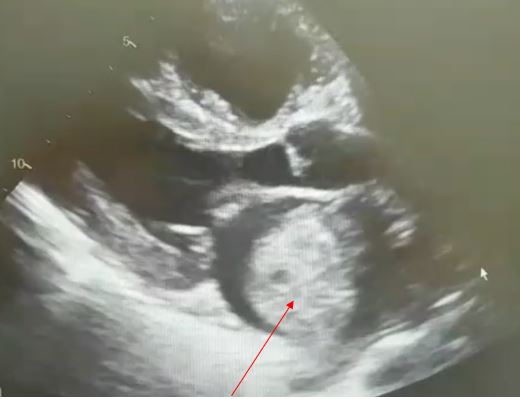

El equipo de cirugía cardiaca del Instituto del Corazón Quirónsalud TEKNON reseca con éxito tres tumores...

El Servicio de Cirugía Cardiaca del Instituto del Corazón del CM Teknon, ha intervenido con éxito a tres pacientes con tumores cardiacos gigantes tipo mixoma.Centro Médico Teknones/red-centros/centro-medico-teknon - 5 de agosto de 2020